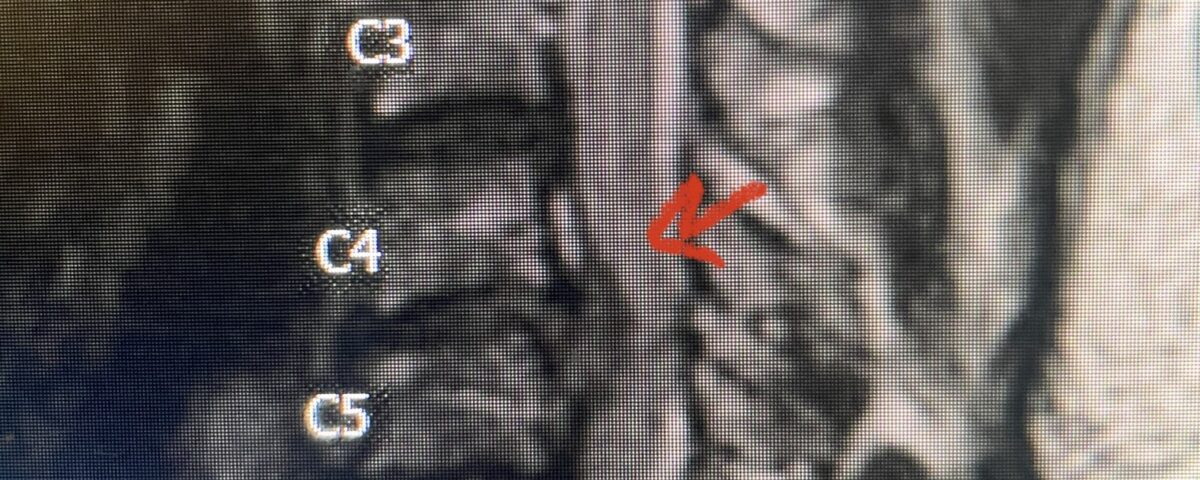

This 47-year-old male who four months prior was lifting weights developed sharp pain in his neck. After that he developed progressive numbness in his arms, neck pain and headache. He said that the right arm was worse than the left. On examination the patient had long tract weakness on the right side which included his triceps, finger extensors, hip flexors, and dorsiflexors. The patient did not have hyperreflexia. MRI (Fig. 2) demonstrated a massive, extruded disc herniation with severe cord compression. The patient because of progressive myelopathy and spinal cord compression was indicated for anterior cervical discectomy and fusion at C4-5 (Fig. 3). Patient had significant improvement of weakness and numbness post operatively.

Fig. 2a Sagittal T2-weighted cervical MRI demonstrating large C4-5 herniated disc with spinal cord compression (red arrow)

Fig: 2b Axial T2-weighted cervical MRI demonstrating spinal cord compression from C4-5 herniated disc (red arrow)